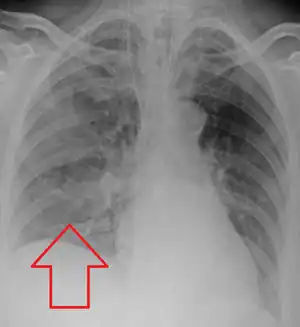

.jpg)

Evaluation of aspiration is generally performed with a video fluoroscopic swallowing study involving radiologic evaluation of the swallowing mechanism via challenges with liquid and solid food consistencies. These studies allow for evaluation of penetration to the vocal folds and below but are not a sensitive and specific marker for aspiration.[15] Additionally, it is difficult to distinguish between aspiration pneumonia and aspiration pneumonitis.[16]

Aspiration pneumonia is typically diagnosed by a combination of clinical circumstances (people with risk factors for aspiration) and radiologic findings (an infiltrate in the proper location).[2] A chest x-ray is typically performed in cases where any pneumonia is suspected, including aspiration pneumonia.[17] Findings on chest x-ray supportive of aspiration pneumonia include localized consolidation depending on the patient's position when the aspiration occurred.[18] For example, people that are supine when they aspirate often develop consolidation in the right lower lobe of the lung.[18] Sputum cultures are not used for diagnosing aspiration pneumonia because of the high risk of contamination.[19] Clinical symptoms may also increase suspicion of aspiration pneumonia, including new difficulty breathing and fever after an aspiration event.[6] Likewise, physical exam findings such as altered breath sounds heard in the affected lung fields may also be suggestive of aspiration pneumonia.[6] Some cases of aspiration pneumonia are caused by aspiration of food particles or other particulate substances like pill fragments; these can be diagnosed by pathologists on lung biopsy specimens.[20]